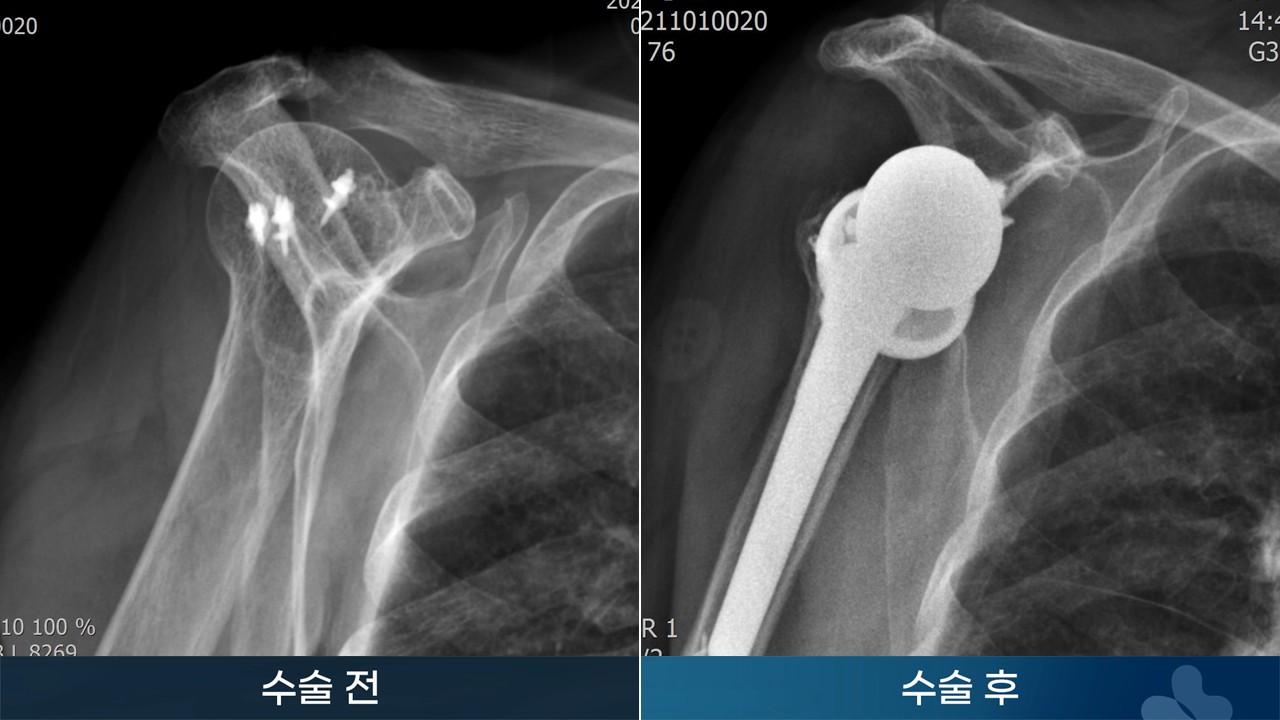

※ 수술 경과는 개인에 따라서 달라질 수 있습니다. 수술 후 멍, 감염, 통증, 부종 등이 발생할 수 있습니다.